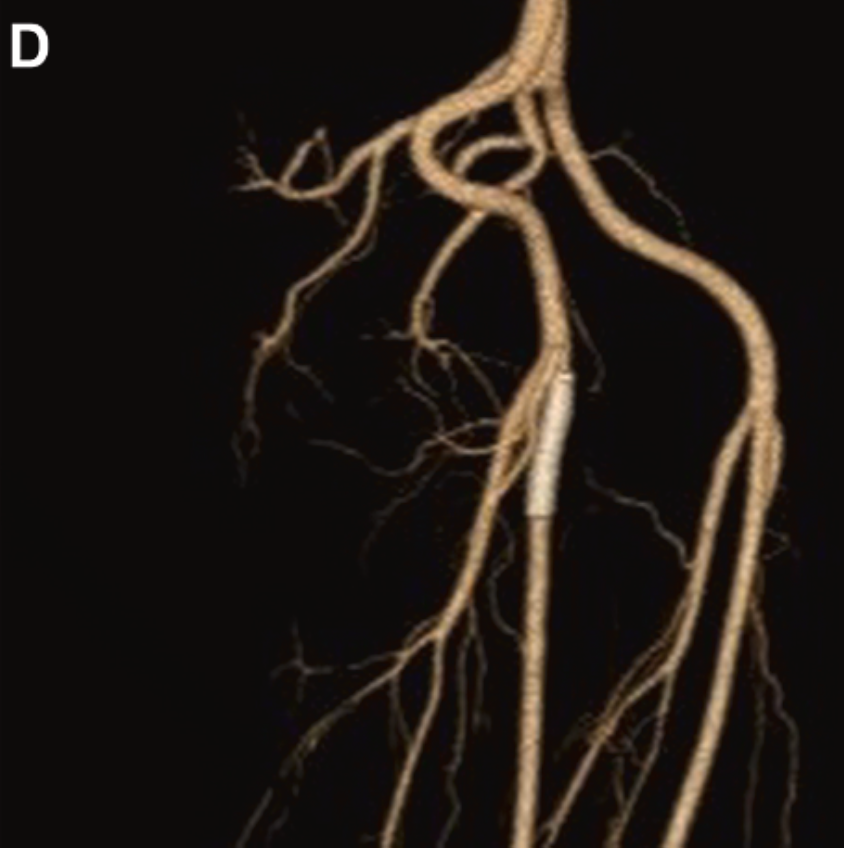

Better visualization, smarter planning. In this JVS-VL pilot study, CEUS + UHFUS showed promise for improving preop mapping and streamlining LVA in patients with lymphedema.